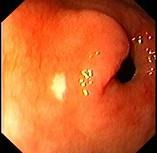

女性,38岁,反复上腹饱胀不适2年,以餐后为甚,伴反酸、嗳气、食欲不振等,体重无明显下降。查体无明显异常。胃镜检查胃窦可见一片状黄色斑块,如下图:该病人最...

问题 女性,38岁,反复上腹饱胀不适2年,以餐后为甚,伴反酸、嗳气、食欲不振等,体重无明显下降。查体无明显异常。胃镜检查胃窦可见一片状黄色斑块,如下图:该病人最可能的诊断是 ( )

选项 A.胃黄斑瘤 B.慢性浅表性胃炎 C.消化性溃疡 D.胃泌素瘤 E.胃癌

答案 A